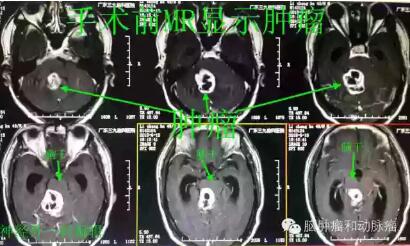

▲MR检查基本确诊为血管母细胞瘤